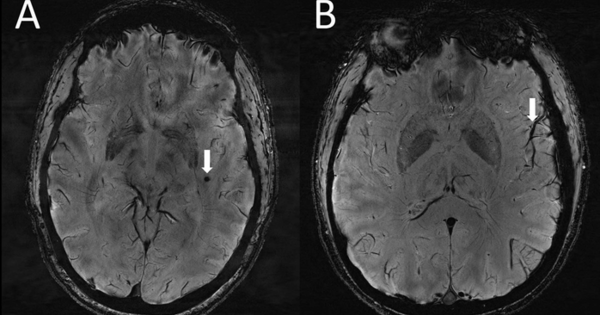

Die strukturelle MRT erzeugt statische Bilder des Gehirns. Sie zeigt die Anatomie des Gehirns und kann verwendet werden, um Veränderungen in der Gehirnstruktur zu erkennen, wie sie beispielsweise bei Tumoren, Schlaganfällen oder Multipler Sklerose auftreten können. Sie kann auch Veränderungen im Volumen bestimmter Hirnregionen erkennen.

Die funktionelle MRT (fMRT) misst die Gehirnaktivität, indem sie Veränderungen im Blutfluss detektiert. Wenn ein bestimmter Bereich des Gehirns aktiver wird, benötigt er mehr Sauerstoff, was zu einer Erhöhung des Blutflusses in diesem Bereich führt. Die fMRT kann also zeigen, welche Gehirnbereiche während bestimmter Aufgaben oder Gedanken aktiv sind. Sie wird häufig in der Forschung verwendet, um die neuronalen Grundlagen von Kognition und Emotion zu untersuchen. In der klinischen Praxis kann sie eingesetzt werden, um die Hirnaktivität bei Patienten mit neurologischen oder psychiatrischen Erkrankungen zu untersuchen.

Obwohl die MRT psychische Erkrankungen nicht direkt "sehen" kann, können bestimmte Veränderungen im Gehirn, die mit diesen Erkrankungen in Verbindung stehen, erkannt werden. Diese Veränderungen sind oft subtil und erfordern spezielle Analysen, um sie zu identifizieren. Es ist wichtig zu betonen, dass keine einzelne MRT-Aufnahme eine psychische Diagnose bestätigen kann. Die Ergebnisse müssen immer im Kontext der klinischen Symptome und anderer diagnostischer Informationen interpretiert werden.

- Schizophrenie: Studien haben gezeigt, dass Patienten mit Schizophrenie Veränderungen im Volumen bestimmter Hirnregionen aufweisen können, insbesondere im Hippocampus, dem Thalamus und dem präfrontalen Kortex. Die fMRT kann auch Unterschiede in der Gehirnaktivität während kognitiver Aufgaben zeigen. DTI-Studien haben Veränderungen in der weißen Substanz gefunden, die auf eine gestörte Kommunikation zwischen verschiedenen Gehirnbereichen hindeuten.

- Depression: Bei Depressionen können MRT-Untersuchungen Veränderungen im Volumen des Hippocampus und des präfrontalen Kortex zeigen. Die fMRT kann eine veränderte Aktivität in Bereichen zeigen, die an der Emotionsverarbeitung beteiligt sind, wie z.B. die Amygdala.

- Angststörungen: Bei Angststörungen können MRT-Untersuchungen eine erhöhte Aktivität in der Amygdala zeigen, einem Gehirnbereich, der für die Verarbeitung von Angst und Furcht zuständig ist. Veränderungen in der Konnektivität zwischen der Amygdala und anderen Gehirnbereichen können ebenfalls beobachtet werden.

- Bipolare Störung: Bei der bipolaren Störung können MRT-Studien Veränderungen im Volumen bestimmter Hirnregionen zeigen, wie z.B. dem präfrontalen Kortex und der Amygdala. Die fMRT kann Unterschiede in der Gehirnaktivität während manischer und depressiver Phasen zeigen.

- Posttraumatische Belastungsstörung (PTBS): Bei PTBS können MRT-Untersuchungen eine verkleinerte Größe des Hippocampus und eine erhöhte Aktivität der Amygdala zeigen. Diese Veränderungen können zu den Symptomen der PTBS beitragen, wie z.B. Flashbacks und übermäßige Schreckhaftigkeit.